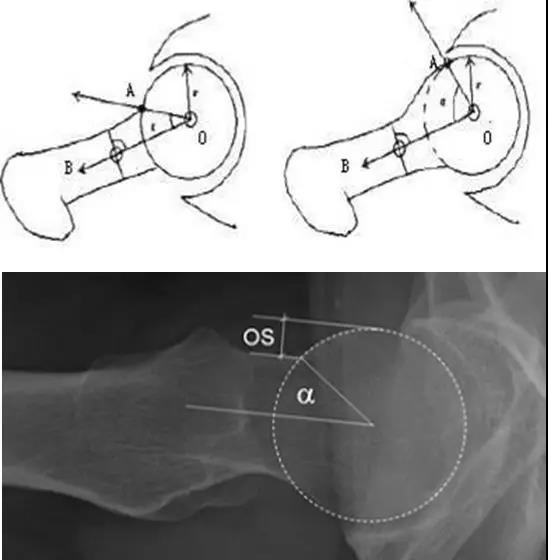

- 股骨头中心O点为圆心,股骨头正常最大半径为r,从股骨头颈连接处骨质与这个圆的交点(A点)到股骨头中心点作直线OA,此直线与股骨颈中轴线OB的交角为α角。

- 反映股骨颈骨赘突出程度,α角越大,越容易发生前上方股骨头颈与髋臼唇的撞击。

- FAI组中该角平均为74.0°±5.4°,正常对照组为42.0°±2.2°。

- α角>50°是诊断FAI的临界值。